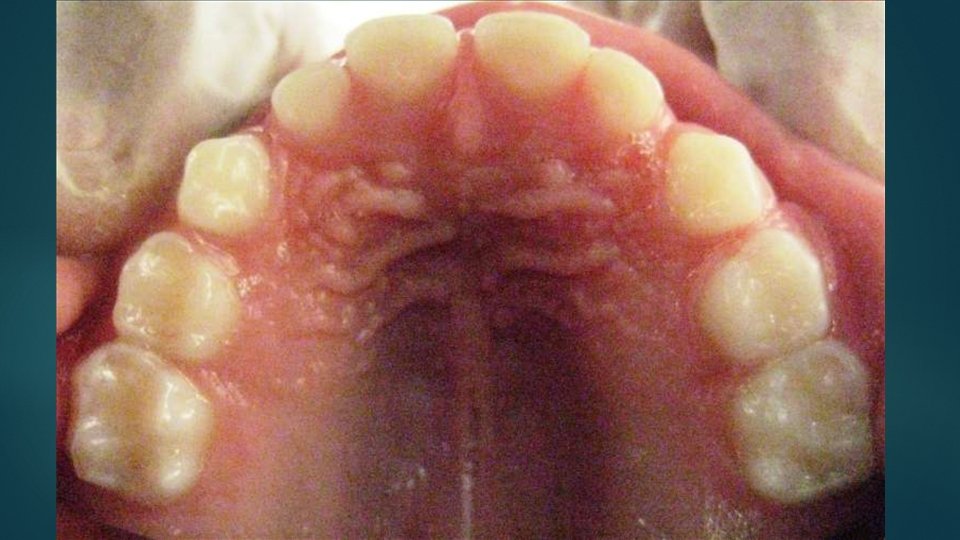

Dentición primaria

Piezas… 20 piezas. 4 incisivos centrales 4 incisivos laterales 4 caninos 4 primeras molares 4 segundas molares

Incisivo central superior… 6 meses Su diámetro mesiodistal es mayor que el cérvico incisal Superficie vestibular suavemente convexa Borde incisal recto Cíngulo desarrollado Raíz cónica

Incisivo lateral superior… 12 meses Más pequeños en todas las dimensiones El alto de la corona es mayor que el ancho mesiodistal Raíz cónica y más larga en proporción a la corona que la del incisivo central

Canino superior… 24 meses La corona es más constreñida en cervical que los incisivos y la superficie mesial y distal es más convexa Cúspide aguda Raíz larga, más del doble de la corona, generalmente desviada hacia distal en apical

Primera molar superior… 18 meses Es más ancho en sentido mesiodistal a nivel de las áreas de contacto y desde ahí converge hacia cervical La cúspide mesial es la mayor y más aguda La cúspide distolingual es pequeña y redondeada Superficie vestibular lisa Tres raíces, largas, delgadas y divergentes

Segunda molar superior… 30 meses Similar al primer molar superior permanente Su corona es mayor que la del primer molar primario Su cara palatina presenta el tubérculo de Carabelli Dos cúspides vestibulares bien definidas con surco de desarrollo entre ellas La superficie palatina presenta la cúspide mesiopalatina más grande y desarrollada, una cúspide distopalatina